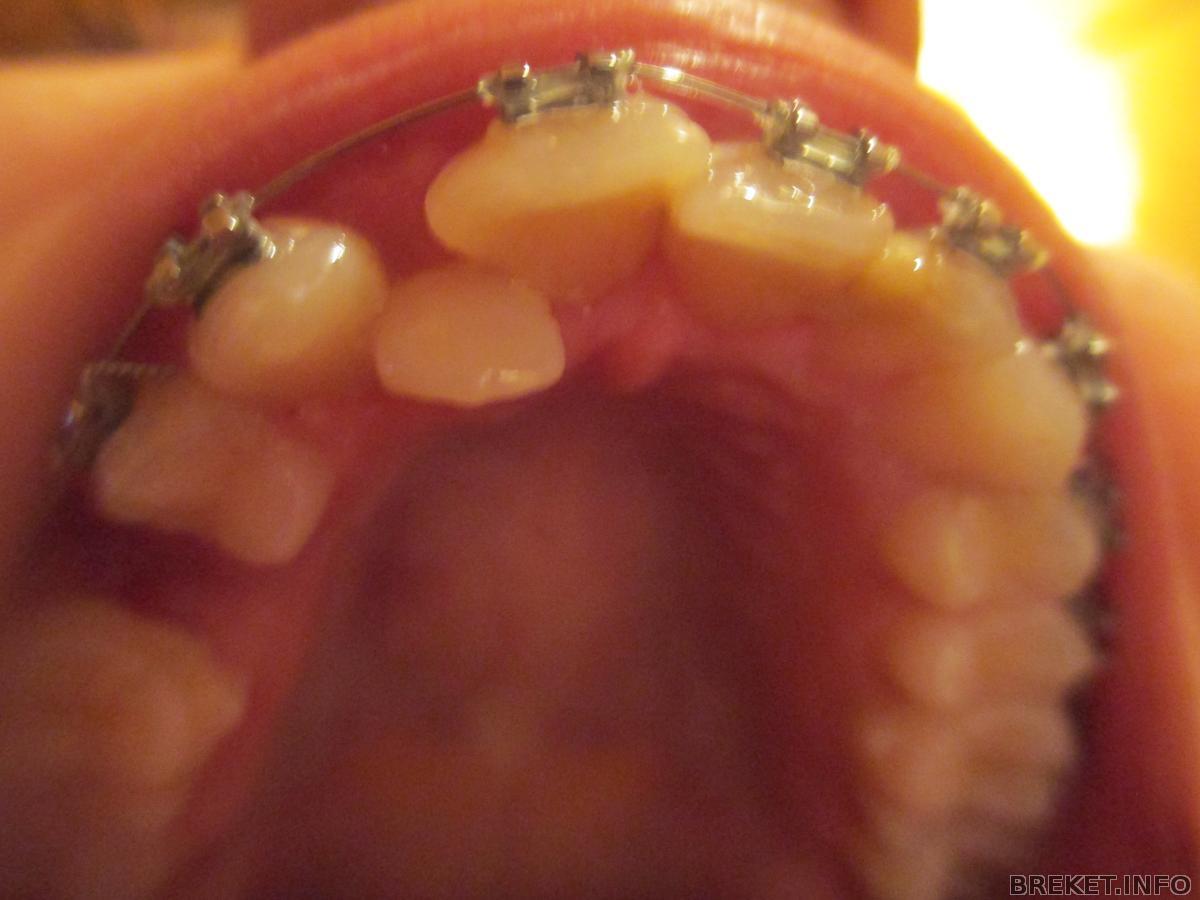

Вообщем,всем привет,моим брекетам уже 2 недели

дуга постепенно выпрямляется

брекеты у меня безлигатурные

эта проволока в помощь клыку

чтобы он опустился